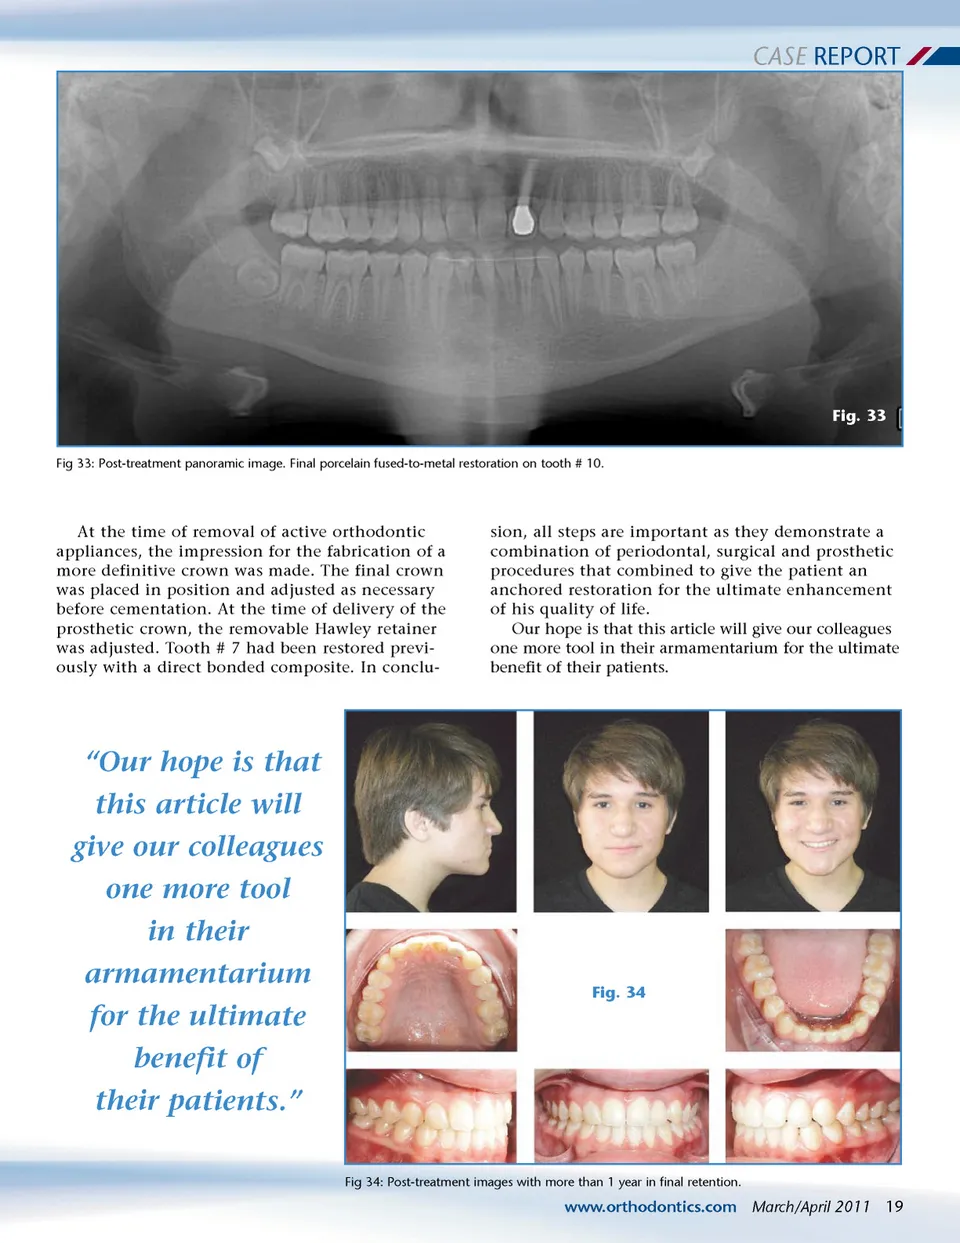

CASE REPORT Fig. 28 Fig 28: Smile image. “...all steps are important as they demonstrate a combination of periodontal, surgical and prosthetic procedures that combined to give the patient an anchored restoration for the ultimate enhancement of his quality of life.” Fig. 29 Fig. 31 Fig 31: Post-treatment lateral cephalometric image. Class I dental with adequate overbite and overjet. Note implant angulation in the alveolar bone. Fig 29: Temporary ready and cemented. Fig. 32 Fig 32: Post-treatment lateral cephalometric tracing. Class I dental, Class III skeletal with dental compensations to mask the Class III skeletal relationship. Fig. 30 Fig 30: Follow-up X-ray. Notice the radiopacity of the flowable composite around the implant collar. sion for the final crown could be taken at the surgical appointment. Conversely, if the implant was solid but the bone felt “softer”, a healing period of 2-4 months is advisable to avoid losing the implant. This protocol has produced an extremely high success rate for the authors. A bracket was placed on the temporary crown to blend in with the brackets on his natural teeth. (Fig 28, 29). 18 March/April 2011 JAOS